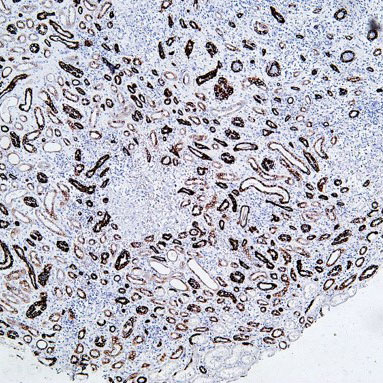

Explore Our Recommended Popular Products

30,000+ high- quality products available online

Primary Antibodies, Secondary Antibodies, mIHC Kits, ELISA Kits, Proteins, Molecular Biology Products,Cell Lines,Reagents ...